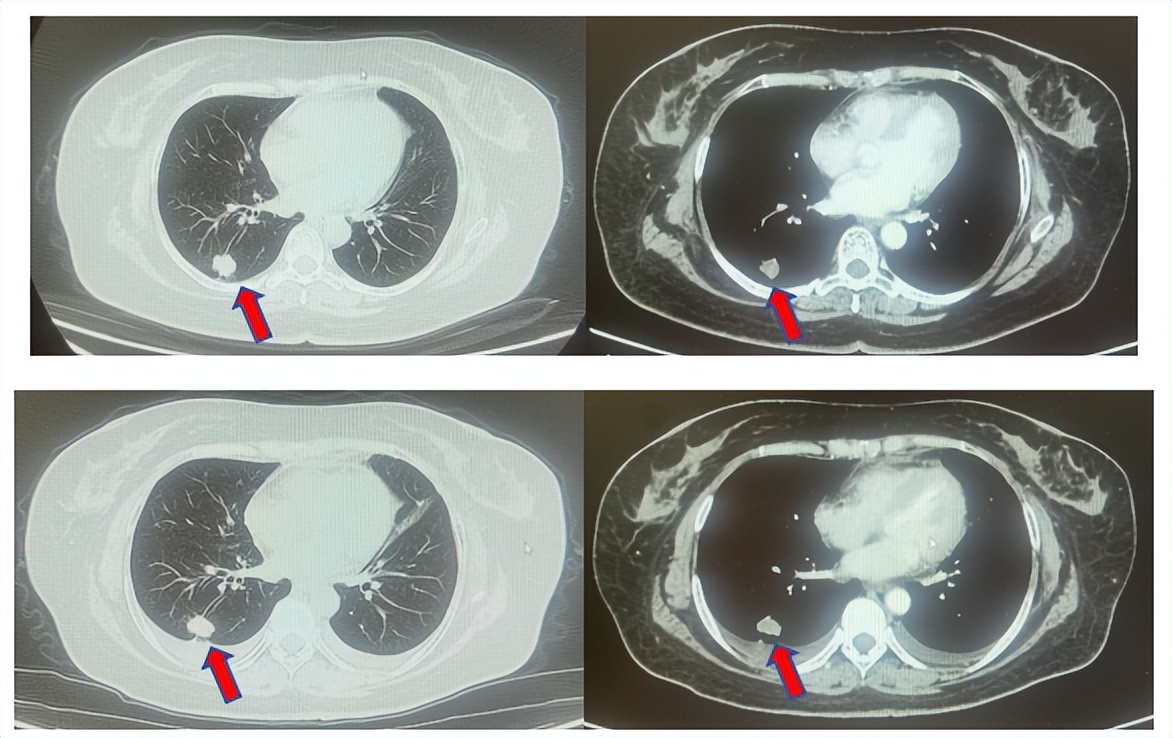

患者进入到二线治疗,该患者再次符合我科“优替德隆对照多西他赛治疗含铂化疗失败的局部晚期或转移性非小细胞肺癌的III期、开放、随机对照临床试验”经随机进入多西他赛组,截止至目前患者已行多西他赛治疗19周期,期间评效为SD(图3),二线无进展生存至今为14个月,患者总生存期截止目前超过92个月(整体治疗过程如图4所示)。

图3:上两图分别展示2024年1月患者一线进展时肺CT肺窗及纵隔窗肺内病灶影像,下两图表示2024年12月患者二线治疗间期评效时肺CT肺窗及纵隔窗肺内病灶影像